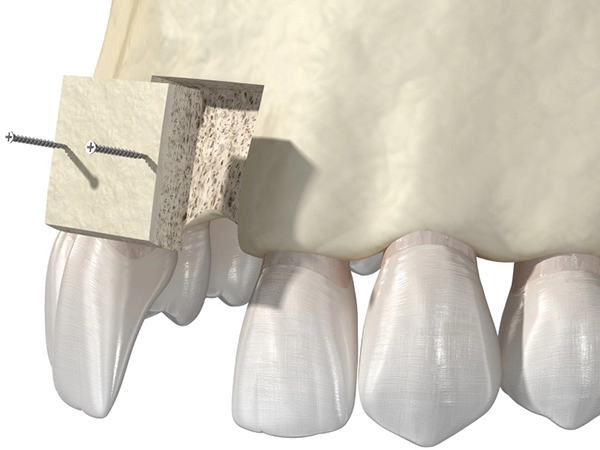

Такой вид операции по остеопластике, как расщепление альвеолярных отростков, проводят путём механического расширения стенок гребня и заполнения образовавшейся полости костным материалом. За счет этого компенсируется нехватка ширины кости. Выполняется одномоментно с установкой имплантатов. Метод применяется для нижней челюсти и на верхней для фронтальной зоны. При сильной вертикальной атрофии (нехватка высоты гребня) метод не применяется.

Такой вид операции по остеопластике, как расщепление альвеолярных отростков, проводят путём механического расширения стенок гребня и заполнения образовавшейся полости костным материалом. За счет этого компенсируется нехватка ширины кости. Выполняется одномоментно с установкой имплантатов. Метод применяется для нижней челюсти и на верхней для фронтальной зоны. При сильной вертикальной атрофии (нехватка высоты гребня) метод не применяется.

Подсадка костных блоков – это операция по изъятию собственного костного материала и подсадка его в дефицитные зоны на нижнюю или верхнюю челюсть. Применяется для восстановления объема костной ткани при установке имплантов.

Подсадка костных блоков – это операция по изъятию собственного костного материала и подсадка его в дефицитные зоны на нижнюю или верхнюю челюсть. Применяется для восстановления объема костной ткани при установке имплантов.